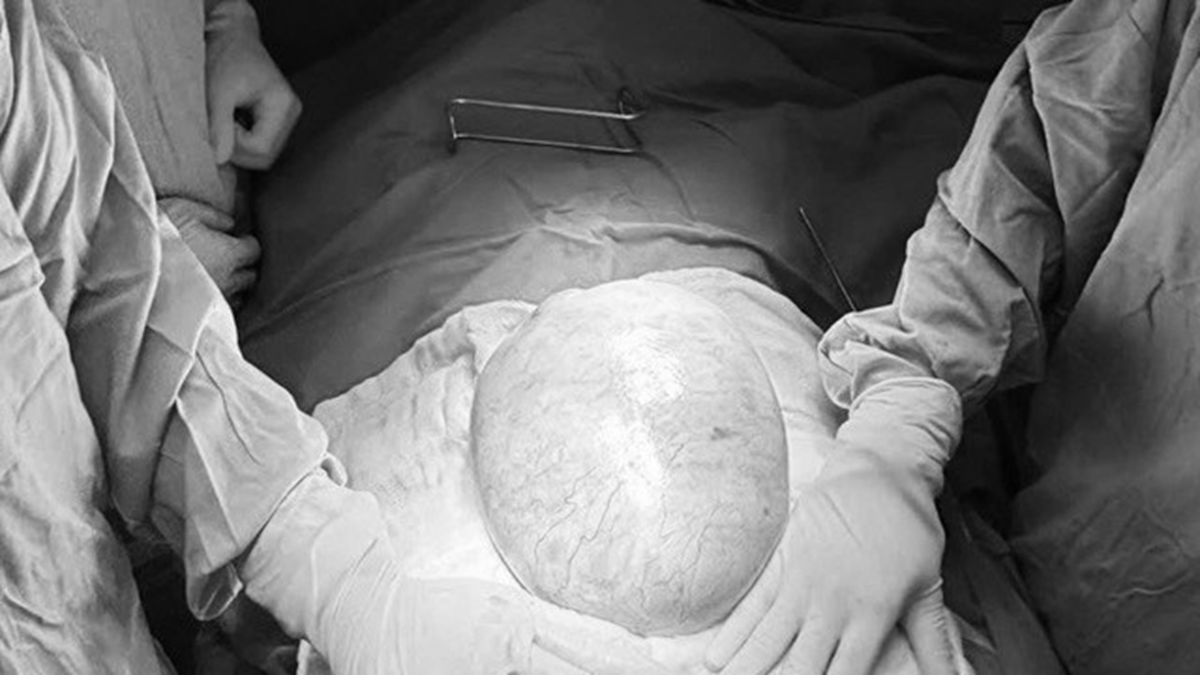

Khối u buồng trứng khổng lồ ở bệnh nhi. Ảnh BVCC.

Khi nhập viện, bác sĩ ghi nhận bụng bệnh nhi mềm, xuất hiện khối vùng hạ vị phát triển vượt qua rốn, ấn không đau. Các xét nghiệm dấu ấn khối u như AFP và beta-hCG đều trong giới hạn bình thường. Tuy nhiên, siêu âm và chụp CT cho thấy, một khối u ổ bụng rất lớn, kích thước khoảng 18-25cm, cấu trúc hỗn hợp gồm dịch và mô đặc. Bên trong khối u có vách, vùng mô đặc, vôi hóa và mô mỡ, gợi ý khối u xuất phát từ buồng trứng phải. Khối u còn chèn ép niệu quản phải, gây giãn niệu quản và thận phải ứ nước.

Theo BS.CKI Nguyễn Hiền (Khoa Ngoại Tổng hợp, Bệnh viện Nhi đồng 2), khi tiến hành phẫu thuật, các bác sĩ ghi nhận khối u có kích thước khoảng 20x25x10cm, nặng gần 4kg, chiếm gần toàn bộ buồng trứng phải. Do khối u lớn, có thành phần mô đặc và nguy cơ ác tính, ê-kíp quyết định cắt trọn buồng trứng phải cùng vòi trứng phải nhằm loại bỏ hoàn toàn tổn thương. Ca phẫu thuật diễn ra thuận lợi, bệnh nhi hồi phục tốt sau mổ.